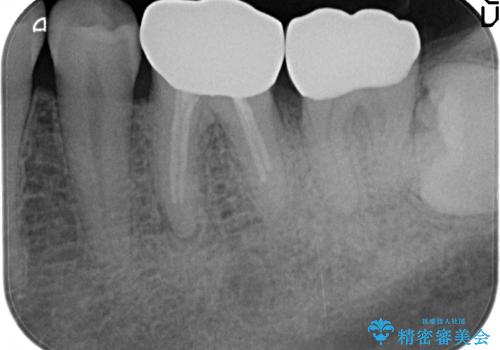

- 左下7の歯しみる、被せ物を被せてもすぐに外れてしまうといらっしゃった方の症例です。

左下に被せ物を被せるクリアランス(補綴のための上下のスペース)ないため、十分な歯冠長を確保するため歯冠長延長術を行いました。

その後歯肉の回復を待ち、フルジルコニアクラウンにて補綴を行いました。